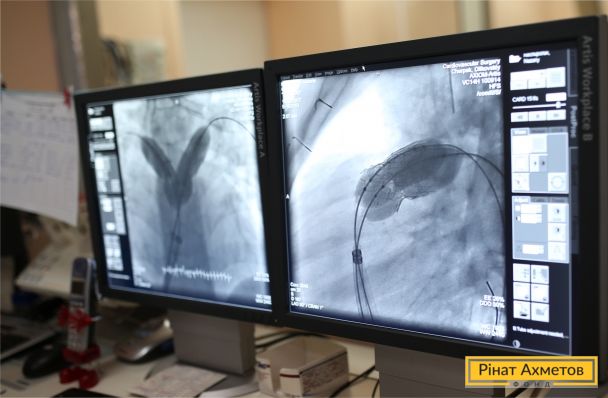

Віршик від 2-річної Елі для лікаря Андрія Максименка, який врятував її маленьке серденько.